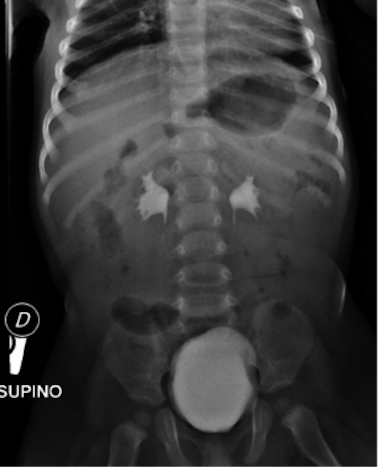

Nel sospetto di una patologia a carico del sistema nervoso centrale (SNC) venivano eseguite TC encefalo con mezzo di contrasto, risultata negativa per masse cerebrali espansive o alterazioni strutturali organiche, e rachicentesi, con fuoriuscita di liquor limpido. Veniva quindi avviata antibioticoterapia empirica ad ampio spettro con ceftriaxone. All’ecografia-FAST eseguita in PS si riscontrava una falda di versamento libero in addome. In virtù di quest’ultimo dato, del persistente stato soporoso e dell’età del paziente, per escludere patologie addominali acute di pertinenza chirurgica veniva effettuato approfondimento radiologico in primis tramite RX addome (Figura 1), risultato poco dirimente se non per la presenza di alcuni livelli idroaerei nel tenue.